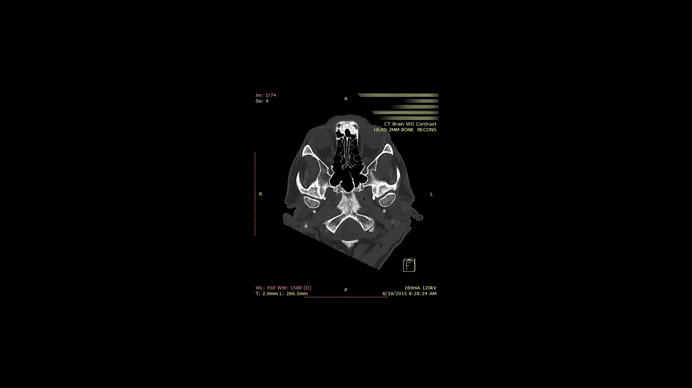

Наша система збирає та інтегрує мультимодальні дані – від детального анамнезу, клінічних показників і результатів медичних знімків (МРТ, КТ, УЗД) до даних лабораторних аналізів, 3D-аналізу рухів та постави, а також висновків спеціалізованих оглядів (наприклад, стоматологічна оклюзія, стан ВНЧС).